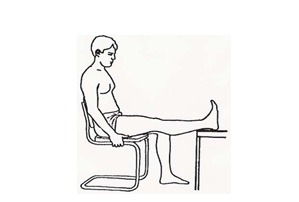

روی صندلی بنشینید، پا را روی صندلی یا چهارپایه بگذارید. هر بار 15 دقیقه در این حالت بمانید. این حرکت را دست کم 3 بار در روز انجام دهید.

روی صندلی بنشینید و عضله ران را حتماً به طور کامل روی صندلی بگذارید. پنجه را بالا بکشید، عضله ران را منقبض کنید و زانو را صاف کنید. 5 ثانیه در این حالت بمانید و سپس استراحت کنید. این حرکت را 10 بار انجام دهید.